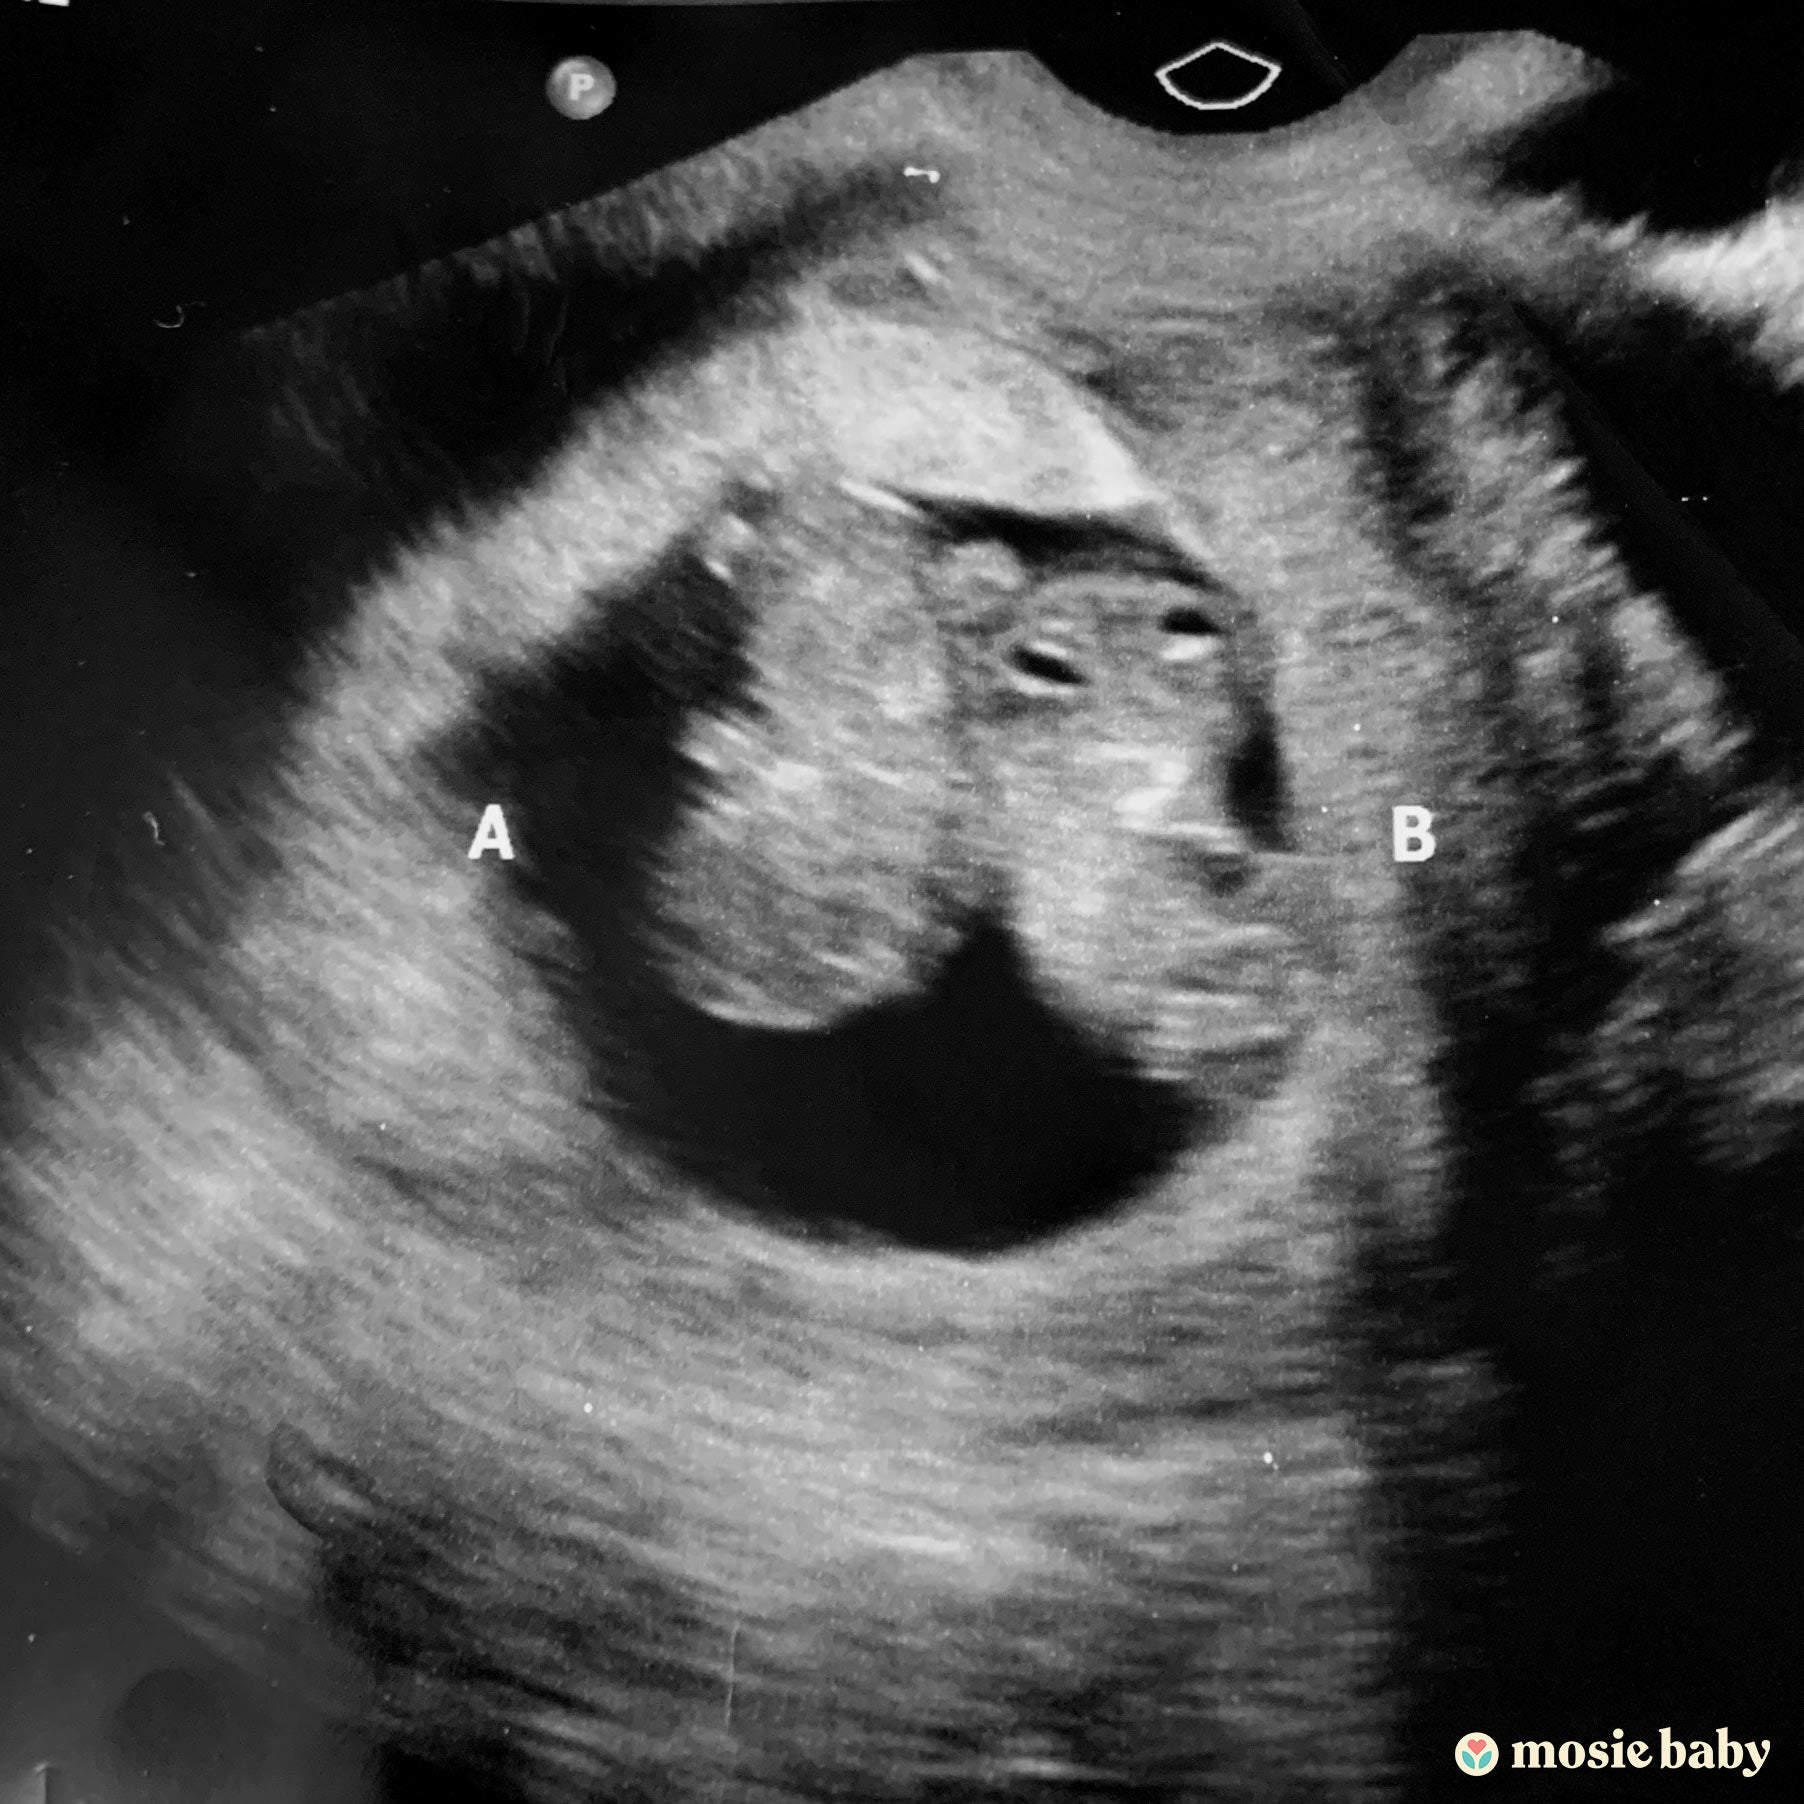

I’m so excited to say that my husband and I are FINALLY expecting, and with TWINS no less!

On our very first cycle with Mosie we were in Walt Disney World for my husband’s birthday and having the Mosie syringes made hitting our TTC days while on vacation stress-free. We were home for two weeks and we got our very first big fat positive ever and many more as I took a total of 6 pregnancy tests that first day, LOL!